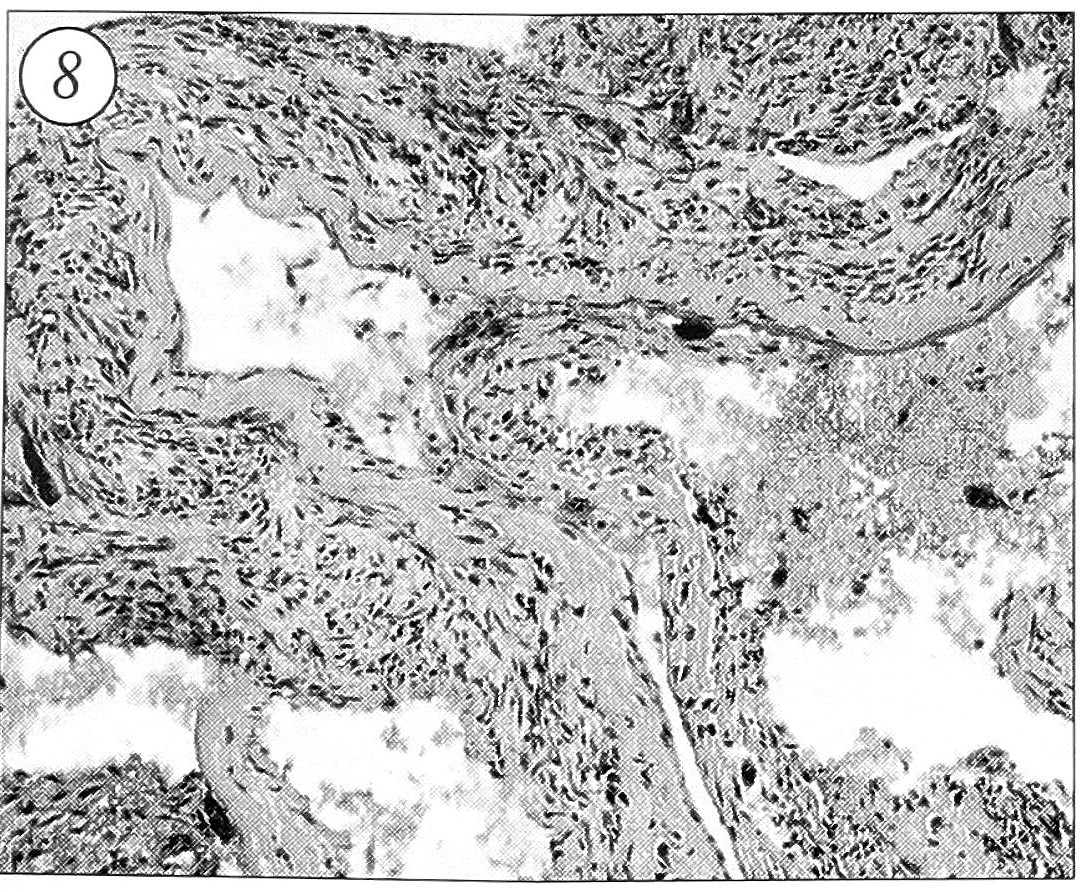

Удаленная при операции патологическая ткань макроскопически была представлена мягко-эластическими оболочками красновишневого цвета с мелкими костными включениями. При гистологическом исследовании выявлена картина аневризмальной кисты кости (рис. 8): ограниченные соединительнотканными перегородками и заполненные кровью кавернозные пространства различного размера, костные балки разной степени зрелости, остеокластоподобные клетки, полиморфные одноядерные клеточные элементы, митотически делящиеся фибробласты и остеобласты, зерна гемосидерина.

Рис. 8. Гистологическая картина: активно растущая аневризмальная киста кости. Полости с элементами крови, разграниченные соединительнотканными перегородками, в которых видны полиморфные фибробласты, гистиоциты, отдельные остеокластоподобные клетки, остеоидные трабекулы. Окраска гематоксилином и эозином, ув. 100.